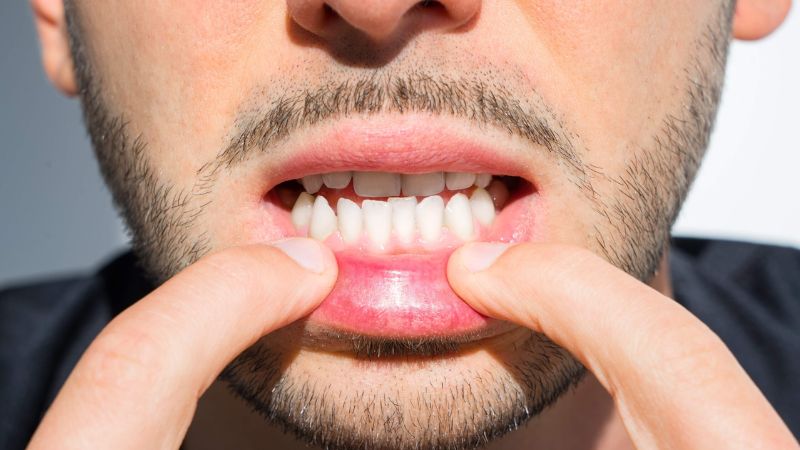

- Móm do răng: Đây là tình trạng răng hàm dưới chìa ra trước so với răng hàm trên, trong khi xương hàm vẫn phát triển bình thường. Niềng răng trong trường hợp này có thể dịch chuyển răng về vị trí đúng trên cung hàm, cải thiện khớp cắn và thẩm mỹ nụ cười.

- Móm nhẹ hoặc trung bình: Những trường hợp móm có sai lệch khớp cắn nhẹ, răng chưa chen chúc nhiều, lực kéo của niềng răng có thể điều chỉnh tương quan răng một cách hiệu quả. Đây là nhóm bệnh nhân thường thấy kết quả gần như hoàn chỉnh sau khi niềng.

- Móm có thể cải thiện bằng khí cụ chỉnh nha: Khi răng và khớp cắn vẫn có khả năng dịch chuyển bằng lực niềng, các khí cụ như mắc cài hoặc khay trong suốt sẽ giúp điều chỉnh răng từng bước, cải thiện độ phủ của răng hàm trên so với răng hàm dưới, từ đó giảm hoặc loại bỏ móm.